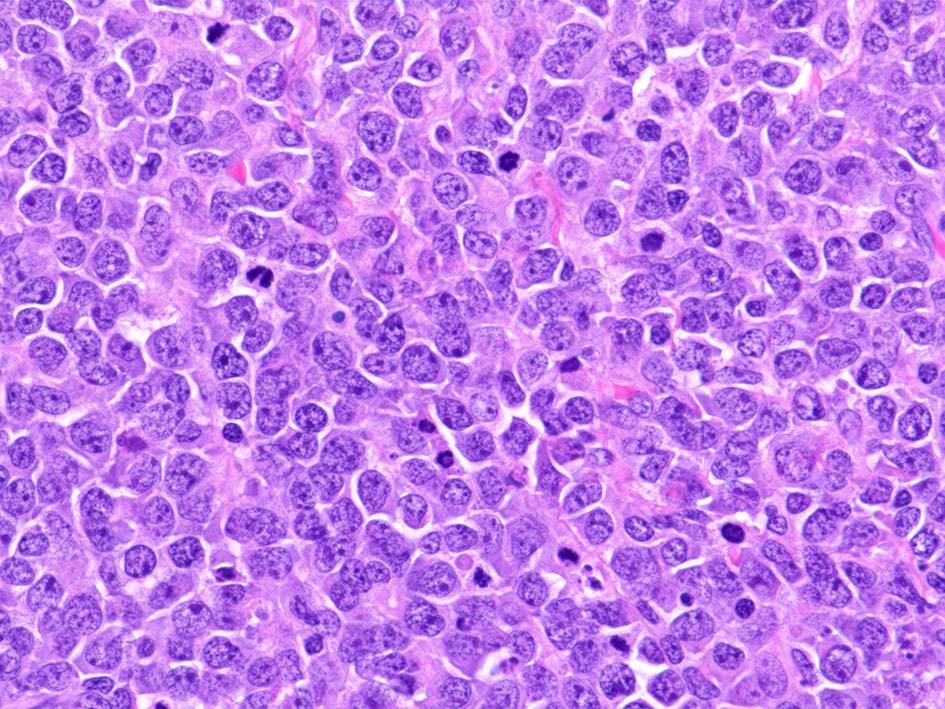

腫瘍細胞はcentroblastic cells. mitosisやapoptosisが多い.

精細管は浸潤により萎縮, 消失. びまん性にcentroblasts/immunoblastsの増殖が認められる. 腫瘍細胞間に軽度の線維化がある.

小リンパ球と同程度か1.5倍くらいのサイズ, round/ convoluted nucleiをもつリンパ球がシート状密に増殖する. 核クロマチンは粗で, 核小体が認められる核もある.

類円形/多稜形の核をもつN/C比大の細胞. 粗大なクロマチンが増加, 核小体は不明瞭. DLBCLに認められるcentroblasts/ immunoblastsの細胞所見と異なる.